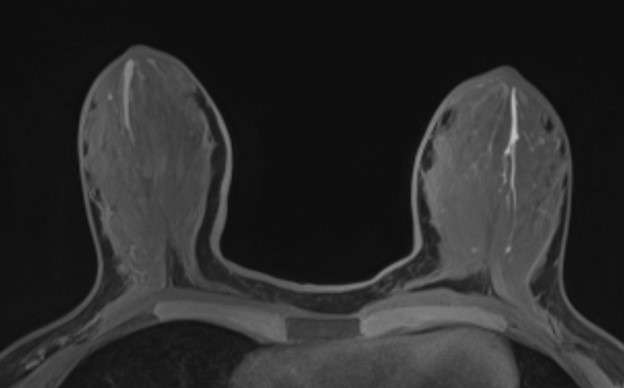

Case: Breast Ductal Anatomy and Function Figure 3

Figure 3: Axial T1-weighted, fat-suppressed, MIP MRI image demonstrates bilateral T1 hyperintense tubular structures arising from the nipple-areolar complex, consistent with proteinaceous ducts